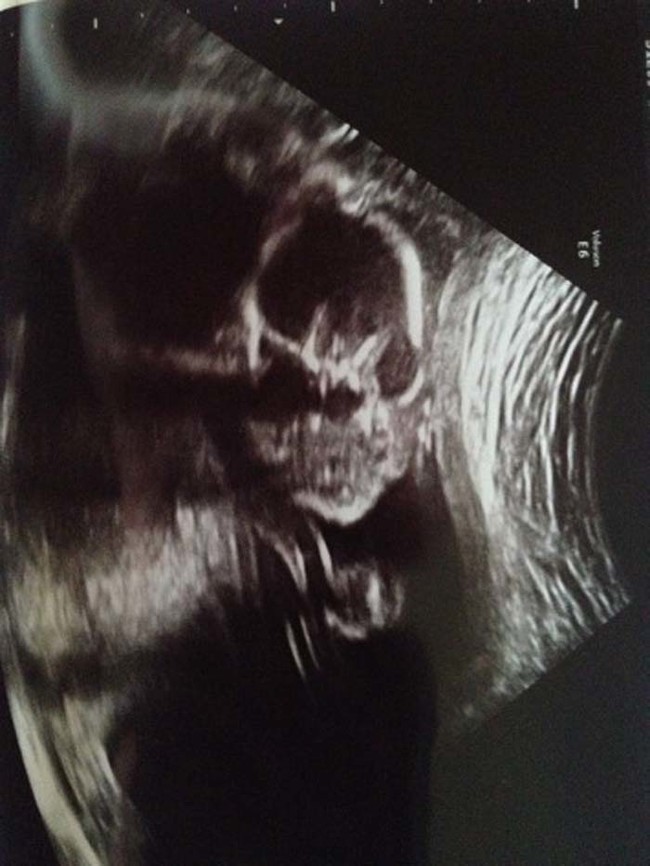

เดี๋ยวนี้ยามตั้งครรภ์คุณแม่เกือบทุกคนก็นิยมอุ้มท้องป่อง ๆ ไปให้คุณหมอทำอัลตราซาวด์ จะได้เช็กดูว่าเจ้าตัวน้อยข้างในอยู่สบายแข็งแรงดีหรือเปล่า แถมยังได้จะเห็นไปหน้าเค้าโครงใบหน้าลาง ๆ ของเจ้าหนูด้วย ดูแค่เงาก็เดาไปกันใหญ่แล้วว่าเหมือนใครมากกว่ากัน จนอดใจไม่ไหวอยากรีบคลอดออกมาให้เห็นหน้าลูกน้อยตัวจริงเร็ว ๆ แต่ถ้ามาเจอ 13 รูปอัลตราซาวด์สุดสยอง ที่เรานำมาฝากจากเว็บไซต์ boredomtherapy เหล่านี้เข้าไปหน่อยล่ะก็... บางทีคุณอาจไม่แน่ใจแล้วล่ะว่า นี่ใช่ลูกฉันจริงหรือเปล่า !!

ถึงจะรักเด็กแค่ไหน แต่ถ้าคุณขวัญอ่อนเราขอเตือนกว่าอย่าเลื่อนลงไปดูดีกว่านะ...